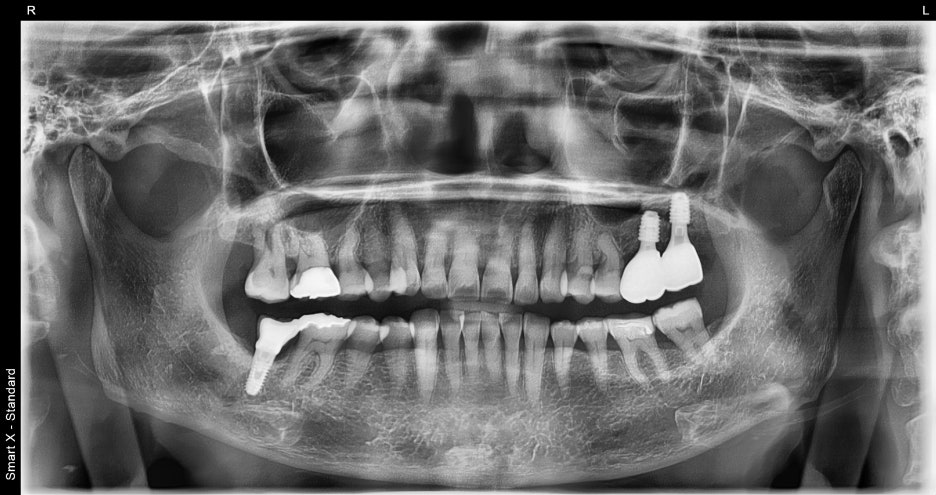

서울오브치과병원에서는 모든 임플란트 치료 전에

3D CT를 촬영합니다.

이번 케이스에서는

#26, #27 주변의 심한 골소실

상악동이 매우 낮아진 상태

치근과 잇몸 사이의 염증

이 확인되었습니다.

특히 상악 어금니는 상악동거상술이 필요한 경우가 많고,

전체임플란트가격이 달라지는 대표적 부위입니다.

환자분도 마찬가지로 단순 식립이 불가능해

GBR(뼈이식)과 상악동거상을 동시에 진행해야 했습니다.

파노라마 엑스레이와 구강내 사진을 통해 확인한 결과,

왼쪽 위 두 개의 어금니가 파절 및 결손 상태

주변 치조골은 비교적 건강하여 뼈이식이

최소화된 상태에서도 임플란트 식립 가능

이라는 진단을 내렸습니다.